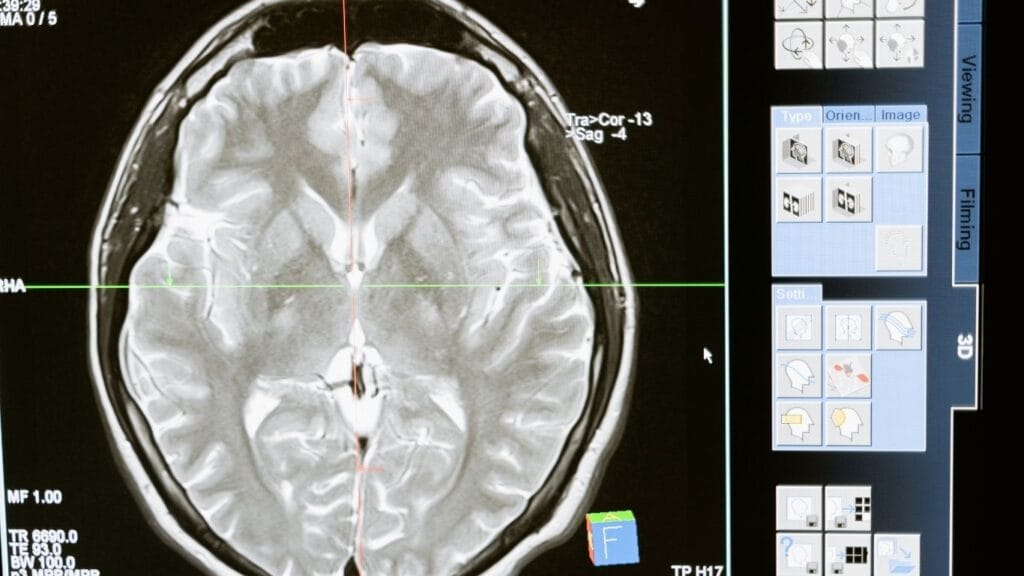

تكلفة جراحة إشعاعية اورام الدماغ في الهند 2025 تعتبر من أبرز المواضيع التي تشغل المرضى الدوليين الباحثين عن علاج فعال